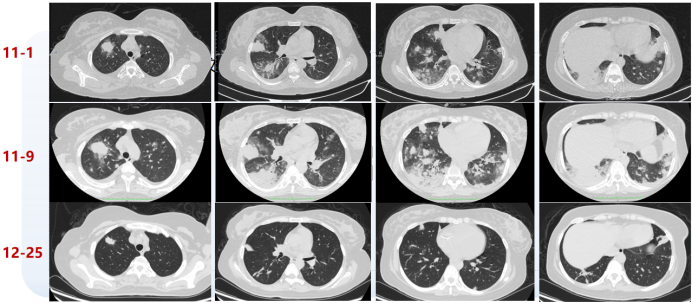

30岁女性患者,发热伴乏力19天,妊娠状态,头孢、青霉素及大环内酯类抗感染治疗效果不佳。

实验室检查示WBC 9.21×109/L,PLT 159×109/L,NEU% 84.6%,LYM 0.98×109/L,Hb 112 g/L(↓)。支气管镜检查未见明显异常,BALF白细胞分类:巨噬细胞75%,淋巴细胞24%,中性粒细胞1%。含铁血黄素(-)。BALF mNGS(DNA+RNA):人疱疹病毒4型(序列数2701),人疱疹病毒6B型(序列数227)。

TBLB病理结果:肺组织,肺泡间隔略水肿、增宽,间质急慢性炎细胞浸润,肺泡腔内组织细胞聚集。病原体染色(抗酸、GMS、PAS)均阴性。

经过抗感染治疗,病情未能得到有效控制,肺部病灶进展,反复发热。考虑为非感染性疾病,选择RB1+RB10进行TBCB,病理诊断为EBV感染相关淋巴组织增生性疾病,高度怀疑EBV相关淋巴瘤。终止妊娠后经PET-CT、骨穿及活检确诊,于全麻下行左颈部淋巴结剥离术+左乳腺穿刺术,后续化疗,复查胸部CT病变较前吸收。

图片

1  患者胸部CT变化情况